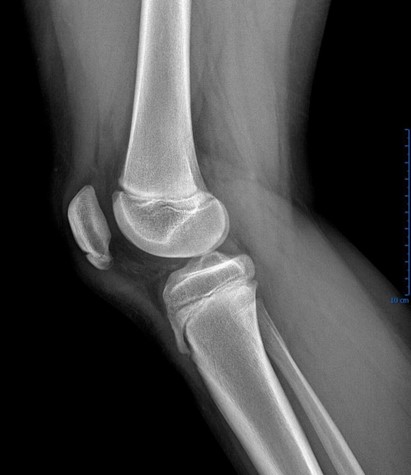

Osgood-Schlatter Disease

This condition is an example of a juvenile apophysitis - inflammation of the area around the growth plate. It is a common overuse condition in children which presents as inflammation of the tibial tubercle apophysis with repetitive extension.15 The exact mechanism of this is unclear, though likely due to repetitive strain across the apophysis due to imbalance of the pull of the quadriceps muscle. The resulting inflammation presents with tenderness as well as pain, with forceful extension directly over the tibial tubercle. While traditionally taught as a condition of males, recent literature reveals no sex difference.16 History and clinical exam is sufficient for diagnosis, but x-rays can be obtained if it is part of a larger differential or if there is concern for a full avulsion. X-rays may demonstrate avulsion so should be obtained if this is considered.9 NSAIDs, rest, and ice are typically effective. Quadriceps and hamstring stretches should be incorporated into routine for all young athletes who have an open physis. Use of a patellar strap can also help decrease pain in some patients. The condition is generally self-limited with resolution after closure of the physis. Conservative management is successful in >90% of patients but operative management is indicated in some patients.16 Prominent tubercle can become permanent and can be a cosmetic concern. Arthroscopy can be performed to intervene on particularly resistant cases.15

Case courtesy of Assoc Prof Frank Gaillard, Radiopaedia.org From the case rID: 7511